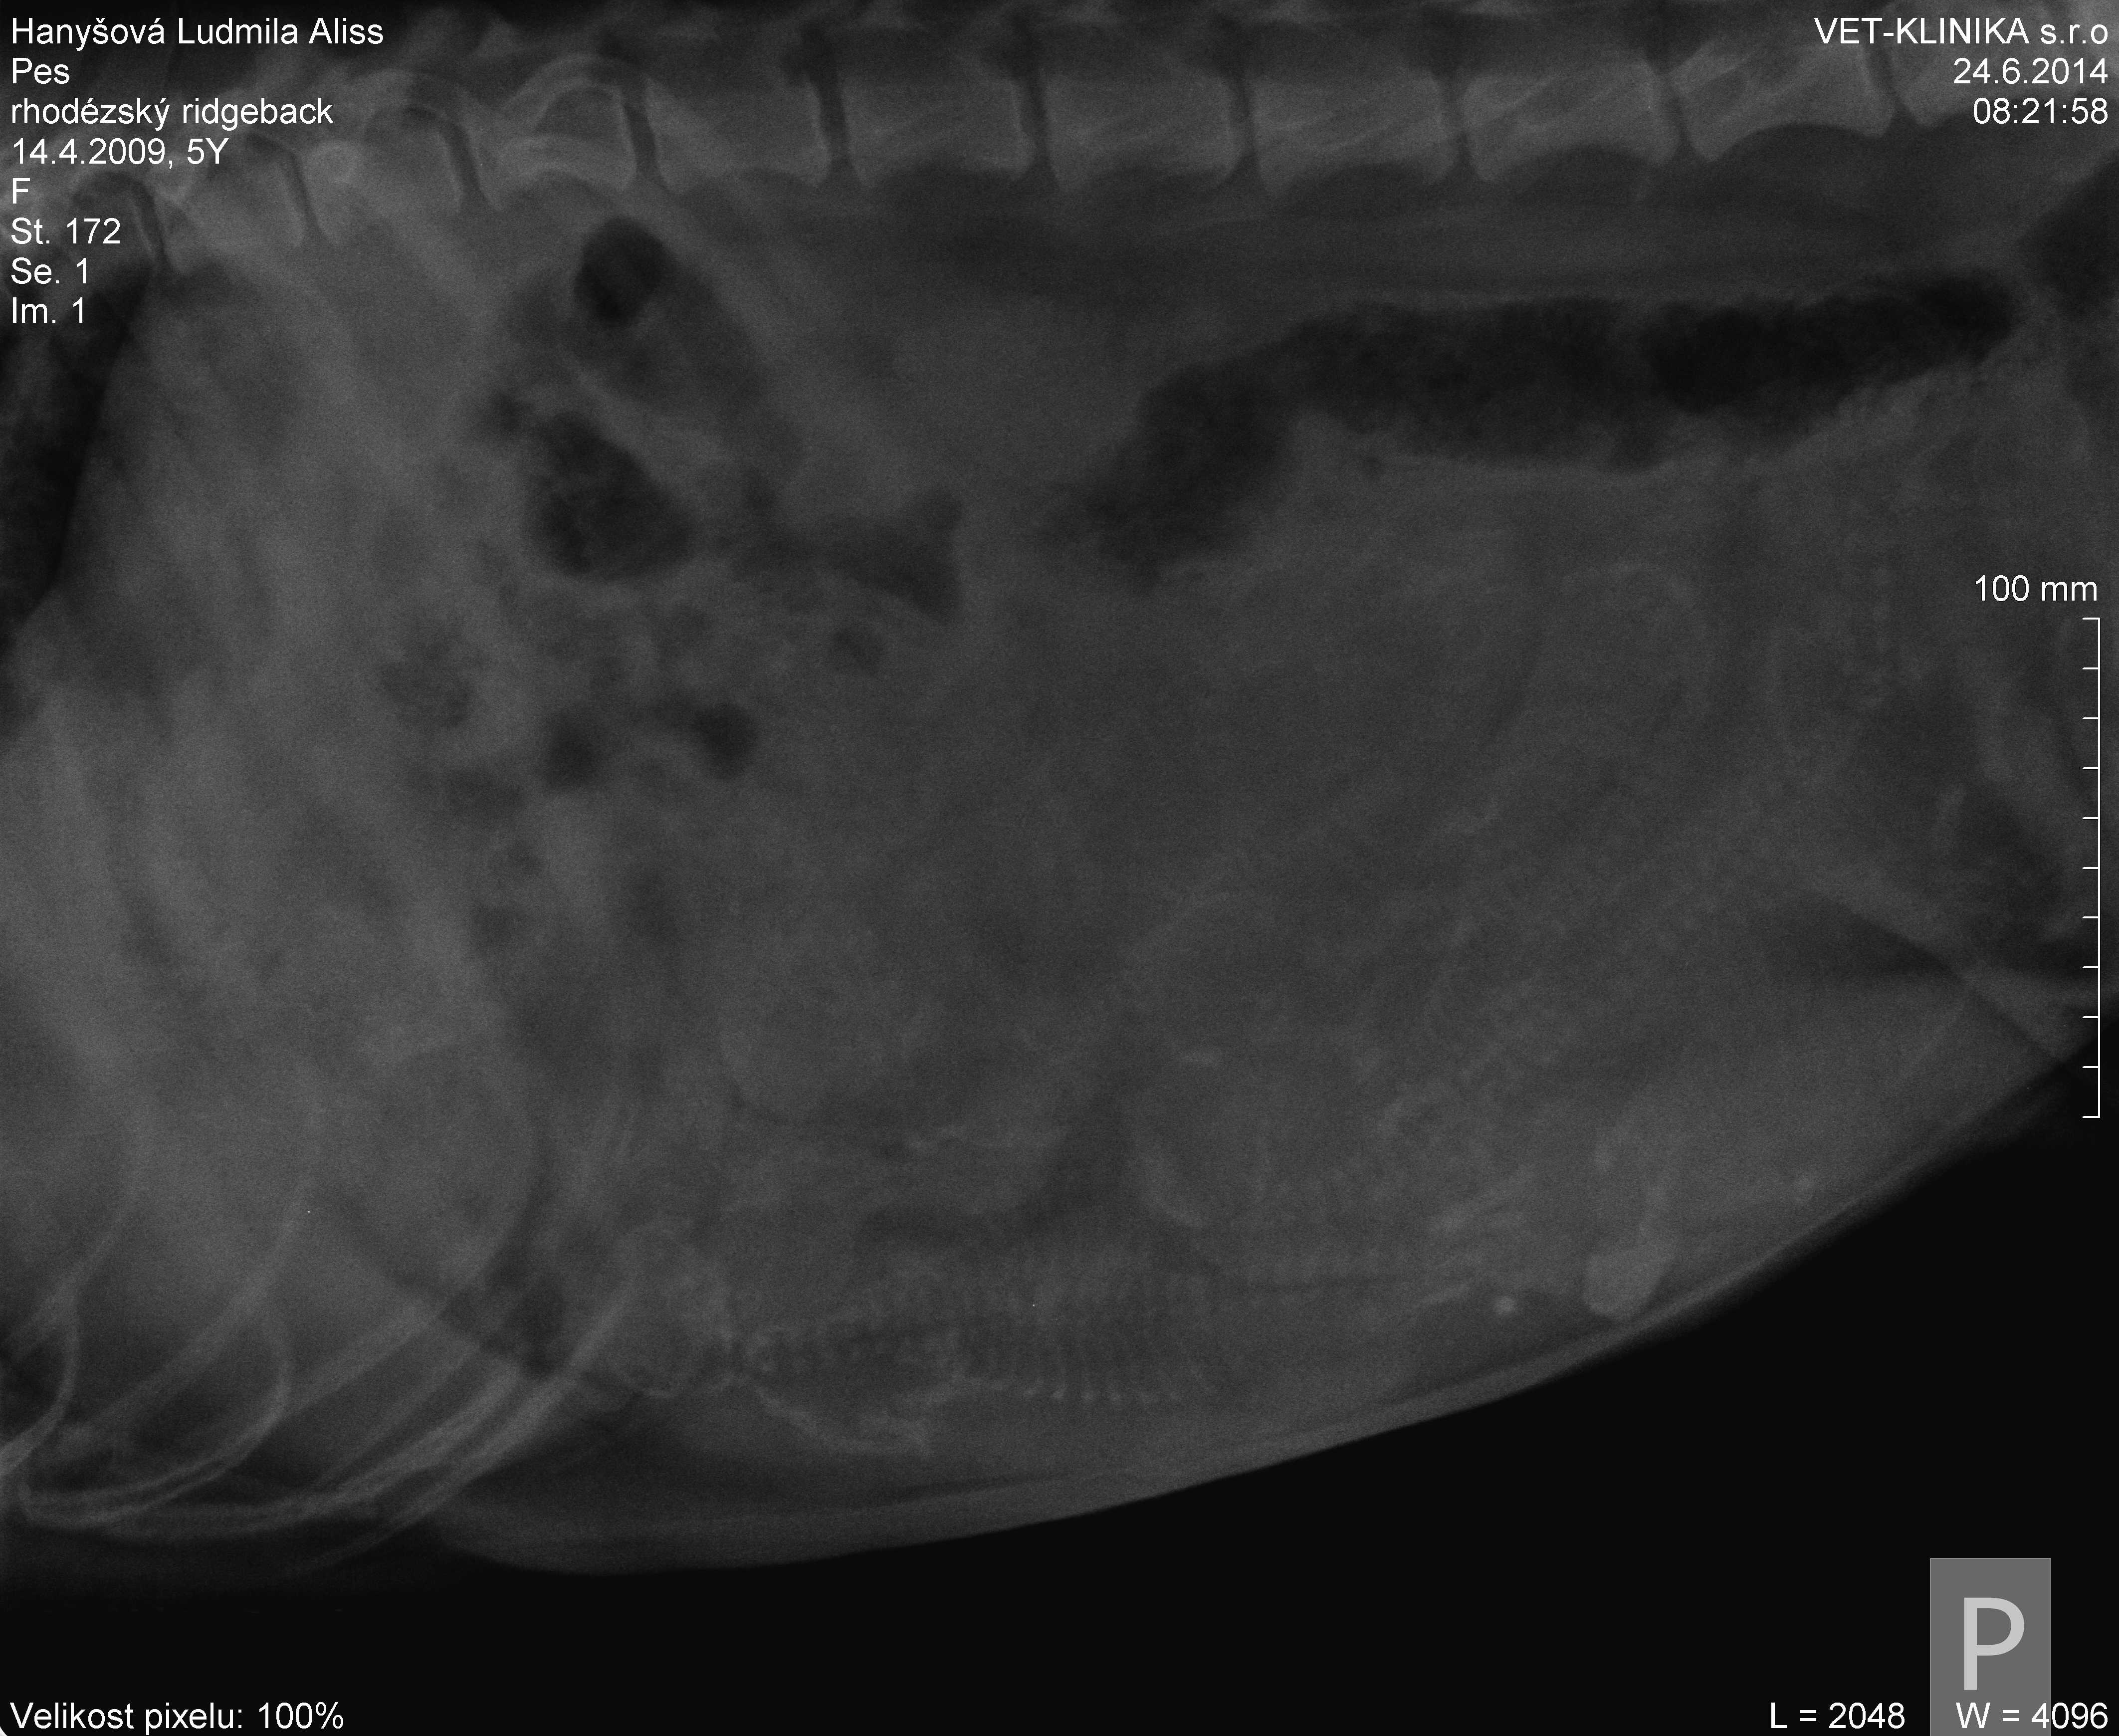

Tak jsme měli tentokrát pocit, že potřebujeme mít jistotu. Už dvakrát nám doktoři říkali, že těch miminek nebude moc...dvakrát jsme skončili s počtem 14. Tentokrát už po sonu říkala paní doktorka, že tohle vážně nebude početný vrh. Faktem je, že jsem měla z Geenky pocity, že si březost užívá, ale že by bylo bříško jóó plné mi rozhodně nepřišlo. A tak jsme se poprvé v životě vypravili nechat si udělat rtg fotečku. No, pan doktor Ekr pravil, že 14 jich rozhodně není a že nám přeje šťastný porod i počet

, ale...Když jsme rtg otevřeli v pc byl mnohem zřetelnější než v ordinaci na velké obrazovce. Myslím, že s počtem 6 - 8 se můžu rozloučit. Řekněte mi, jak to vidíte vy?